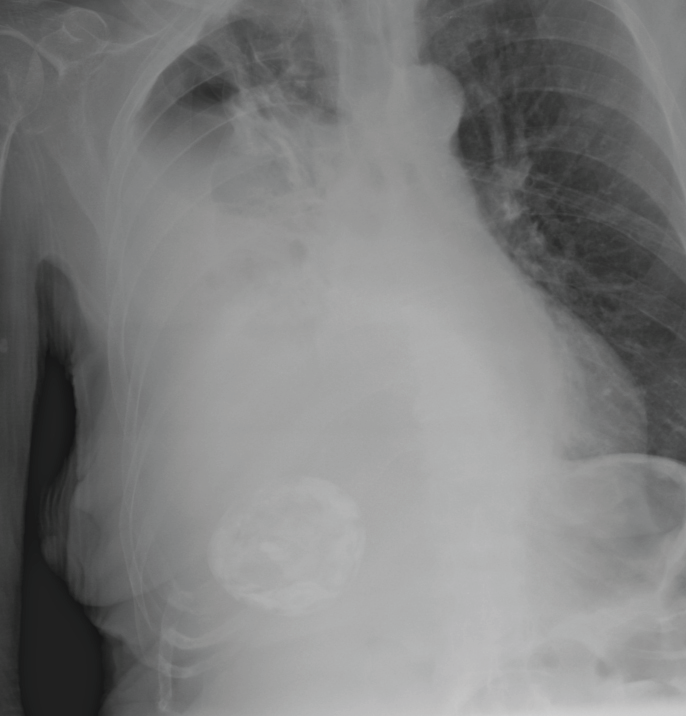

A 75-year-old female patient with past medical history of severe Alzheimer's disease, totally dependent with nasogastric tube feeding (NGT) presented to the emergency department with worsening dyspnea in the past 48 hours. Physical examination revealed on auscultation decreased air entry over the right lung and dullness to percussion. Two days before admission the patient had the NGT changed and a chest X-ray to corroborate position that was checked by one of the junior doctors and discharged to the nursing home. A thoracic bedside ultrasound demonstrated right pleural effusion. A chest radiograph revealed malposition of the NGT in the right pleural space and hydropneumothorax, the NGT was immediately removed without complications and thoracic drainage was inserted obtaining 1200 ml of enteral nutrition (Figure 1, Figure 2, Figure 3 and Figure 4). Her hospital course was satisfactory, and the patient was discharged 7 days later.

Figure 1: Nasogastric tube in the right hemithorax.